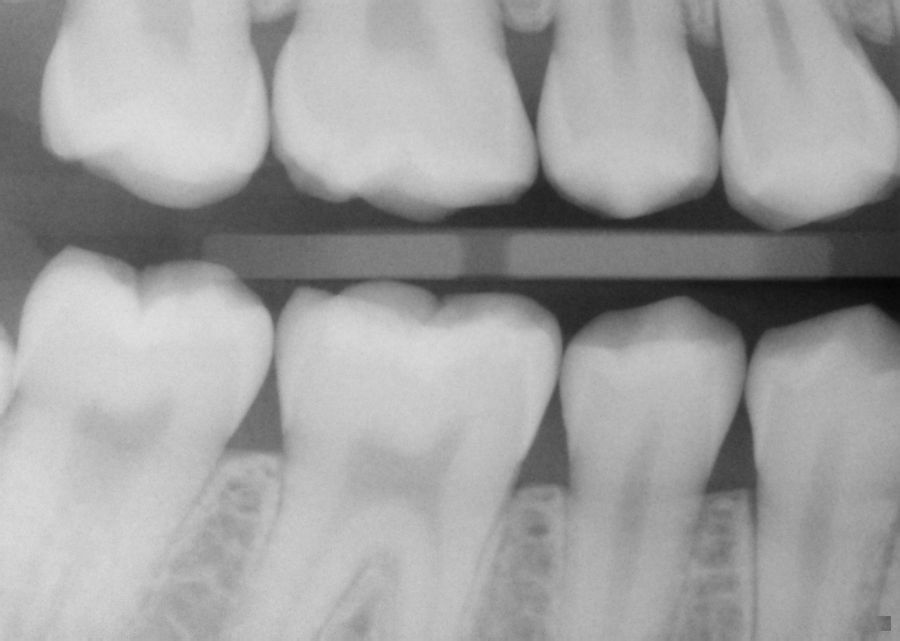

Dental XRay of a 50 year old man with one tooth having a cavity and an Abscess X Ray Tooth Anyone, from children to the elderly, can get one. It needs prompt treatment to prevent. Dental (periapical) abscesses are an acute infection of the periapical tissue around the root of the tooth. A tooth abscess is a severe dental condition characterized by a localized collection of pus caused by a bacterial infection. A tooth abscess is a painful infection at. Abscess X Ray Tooth.